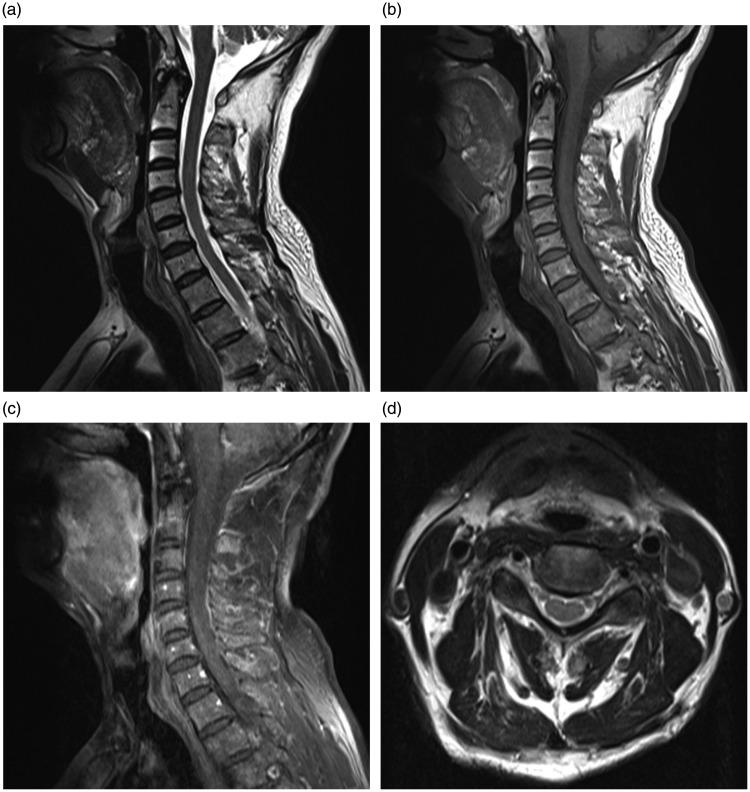

This report describes a case of idiopathic cervical spinal subdural haematoma (SSDH) in which the haematoma was spontaneously absorbed without any treatment. A 68-year-old male patient presented with persistent neck pain and no obvious cause. Magnetic resonance imaging (MRI) revealed a space-occupying lesion at the C4-T1 levels. The lesion was initially misdiagnosed as a tumour. An operation was arranged to remove the tumour, but a preoperative computed tomography scan showed no obvious abnormal soft tissue density in the cervical spinal canal. Repeat enhanced MRI showed degeneration of the cervical vertebrae, but no obvious abnormal soft tissue density and no obvious enhanced signals in the cervical spinal canal. Spontaneous resolution of an idiopathic cervical SSDH was considered. Idiopathic cervical SSDH without obvious neurological symptoms are difficult to diagnose, so suspected cases should be carefully monitored. If the neurological symptoms grow progressively more debilitating with time, emergency surgery might need to be considered. To avoid unnecessary surgery, conservative management should be an option for patients with minimal neurological deficits and re-examination with MRI could be the best way to observe the dynamic changes taking place in the idiopathic cervical SSDH.

本报告描述了一例特发性颈段脊髓硬膜下血肿(SSDH),该血肿未经任何治疗便自行吸收。一名68岁男性患者出现持续性颈部疼痛且无明显病因。磁共振成像(MRI)显示C4 - T1水平有占位性病变。该病变最初被误诊为肿瘤。安排了手术以切除肿瘤,但术前计算机断层扫描显示颈椎管内无明显异常软组织密度。重复增强MRI显示颈椎退变,但颈椎管内无明显异常软组织密度且无明显强化信号。考虑特发性颈段SSDH自行消退。无明显神经症状的特发性颈段SSDH难以诊断,因此对疑似病例应仔细监测。如果神经症状随时间逐渐加重,可能需要考虑紧急手术。为避免不必要的手术,对于神经功能缺损最小的患者,保守治疗应是一种选择,而MRI复查可能是观察特发性颈段SSDH动态变化的最佳方法。